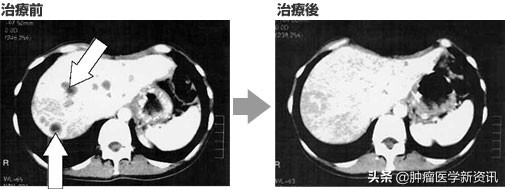

肝脏CT也看到数十处肿瘤,肿瘤标志物AFP也高达1966(正常值为10以下)。

后来,患者肝转移的肿瘤全部消失,肿瘤标志物也回到正常值。